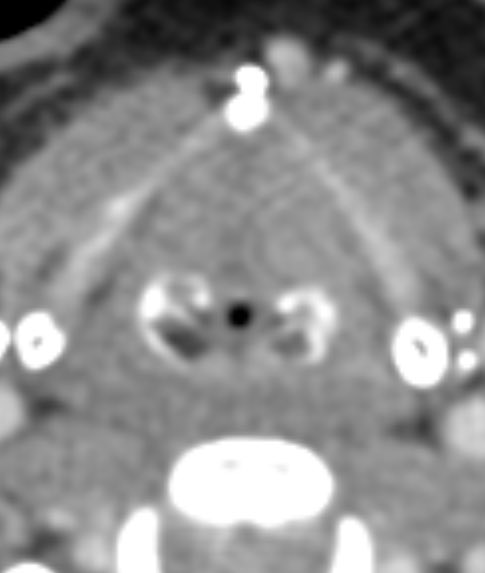

4️⃣Ganglioglioma

▶️Occurs in children and young adults

▶️Location: Temporal lobe (most common)

Imaging (variable and can look very similar to PXA):

▶️Classically presents as a cystic and solid mass in the temporal lobe in a child/young adult with seizures

▶️Presence of CALCIFICATIONS & LACK OF DURAL TAIL may help to differentiate from PXA ImageImageImage